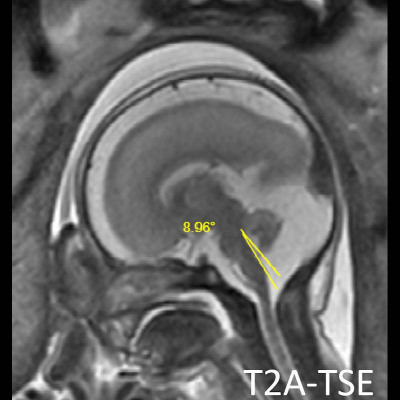

- A) USG incelemede serebral kortikal yapılar düzleşmiş (ok), gyrus sayısı azalmıştır (ok). Kalın ve ekojenik korteks mevcut olup korteks -beyaz cevher ayrımı silik görünümdedir. Posterior fossada ekstraaksiyel BOS mesafesi artmış görünümdedir (ok).

- B) Aksiyel ve sagittal T2A görüntülerde gyrus ve sulkuslarda azalma mevcut olup korteks kalınlaşmış görünümde ve operkulizasyon ayırt edilememiştir. Korteks beyaz cevher ayrımı zor seçilmektedir (ok) Ekstraaksiyel BOS mesafesi artmış görünümdedir (ok). Yapılan ölçümlerde; tegmentovermian açı :8 derece (ok) serebellar vermis boyutları kraniokaudal: 16 mm, aksiyel: 5,5×8,5 mm (ok) ölçülmüş olup BPD:27w ile uyumlu olan fetüste haftasıyla uygun olarak değerlendirilmiştir.

- Dandy Walker Malformasyonu(DWM); posterior fossa ve serebellar vermiş gelişim bozukluğudur. Radyolojik incelemelerde vermisin hipoplazi/aplazisi, tentoryum serebellide superiora yer değiştirme , tegmentovermian açının 45 derecenin üstünde olması ile tanı konur. İntrauterin dönemde bu açı sınırı fetüs gestasyonel haftasına göre değişkenlik göstermektedir.